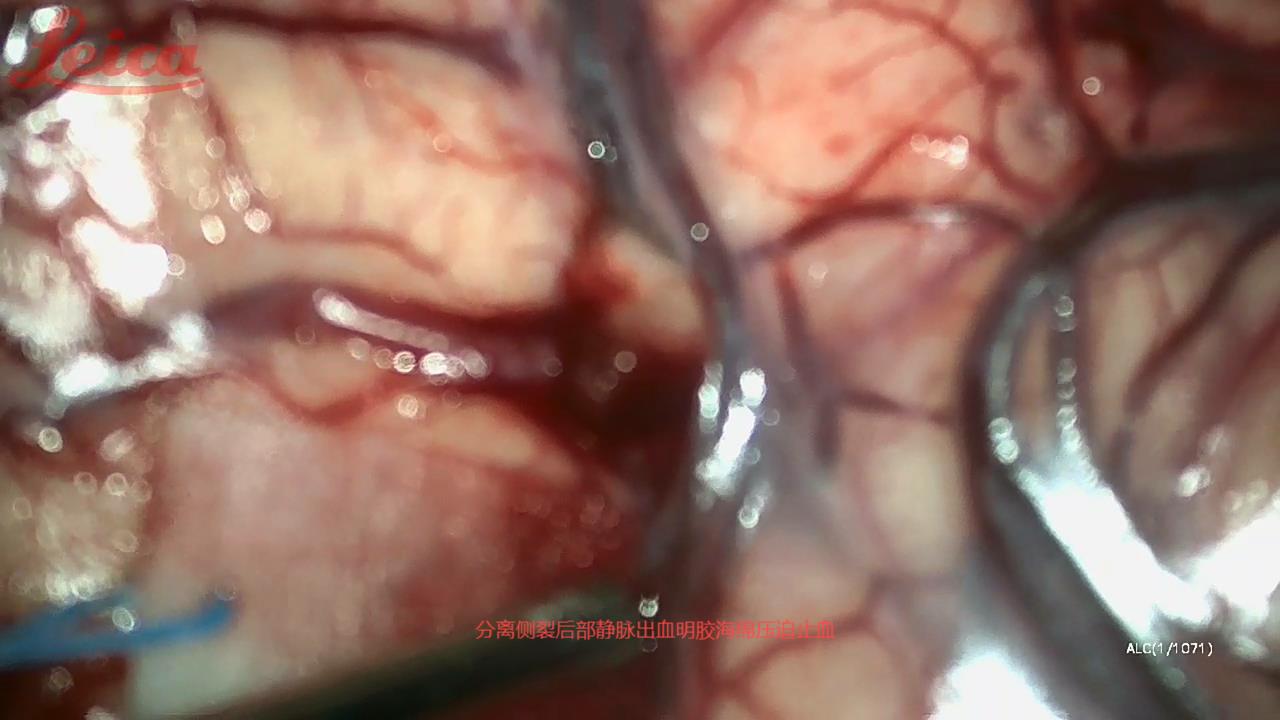

经外侧裂-岛叶造瘘清除血肿简要

经外侧裂-岛叶造瘘清除基底节出血